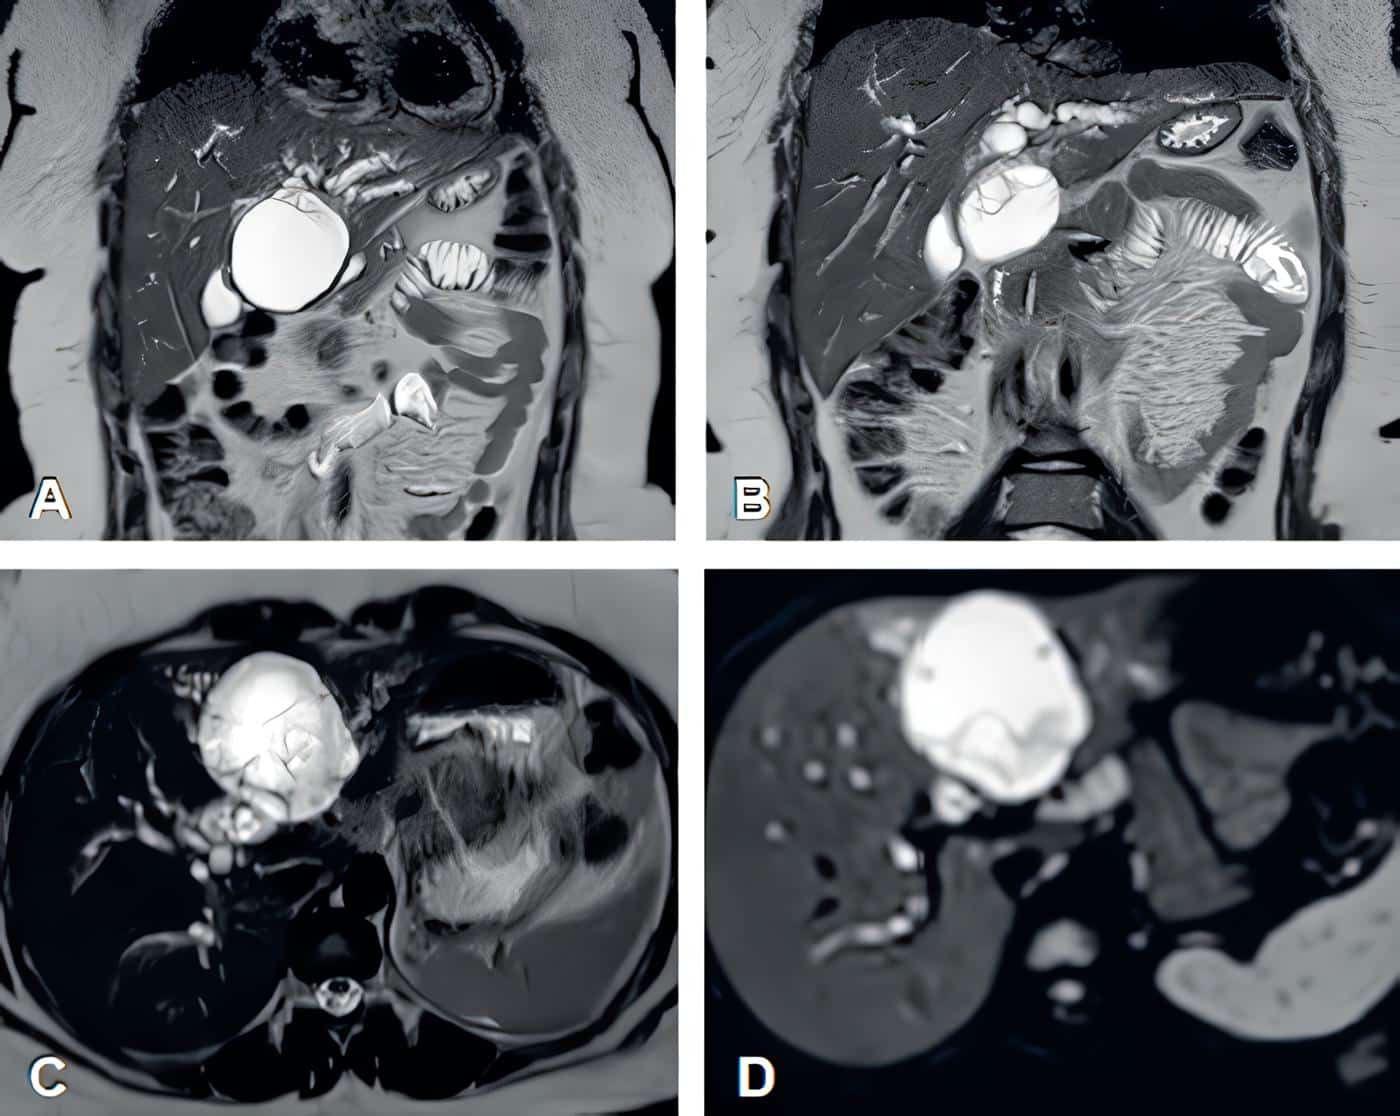

Dados los hallazgos se realizó una colangiorresonancia en la que se observó una lesión quística multiseptada de 63 x 60 mm en el segmento IVB del hígado, marcadamente hiperintensa en T2 (Figura 1), con componente exofítico, comunicada con la vía biliar intrahepática izquierda, con septos delgados que realzaban al medio de contraste y focos menores de 6 mm restringidos en la difusión tisular. La lesión comprimía el conducto hepático común, causando dilatación de la vía biliar intrahepática en ambos lóbulos.

Figura 1. A-B. Cortes coronales de colangiorresonancia en secuencia T2 donde se observa la imagen quística, resaltada en color blanco. C-D. Cortes axiales de la lesión donde se aprecia la difusión tisular restringida. Fuente: elaboración por los autores.